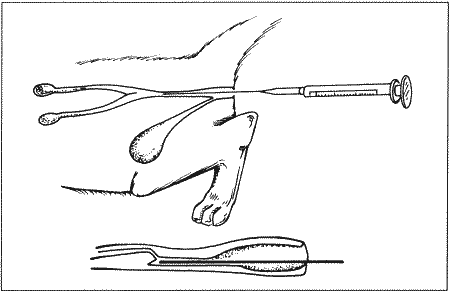

• исследование влагалища у сук методом пальпации и с применением эндоскопа (у кошек подобное исследование затруднительно, см. раздел Методы диагностики, вагиноскопия);